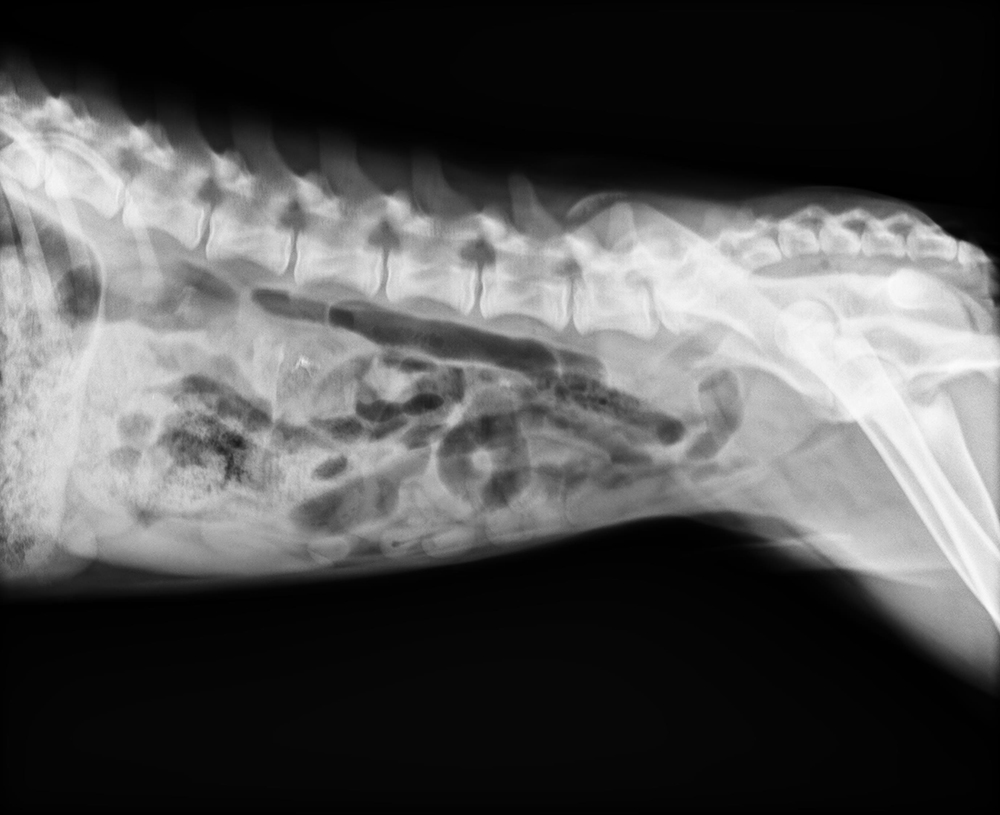

上海鵬峰寵物醫(yī)院